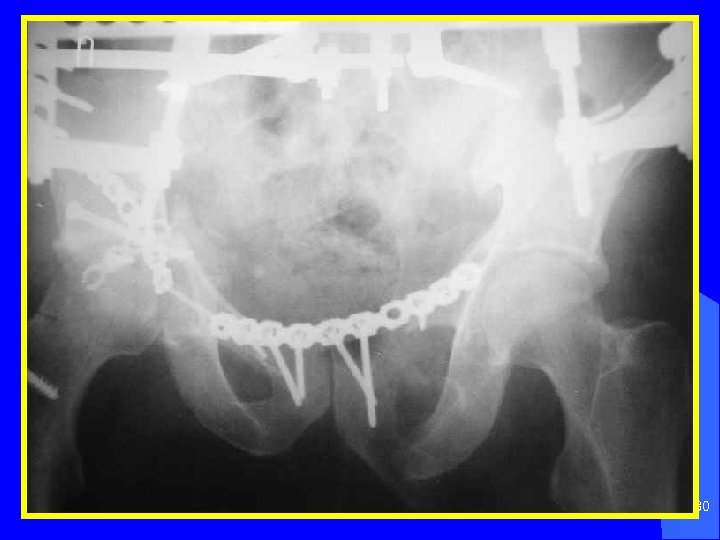

Больные с разрывом симфиза, крестцово подвздошного сочленения лечатся в гамаке до 6 недель. Оперативное лечение показано при отрывных переломах и безуспешном консервативном лечении переломов симфиза и вертлужной впадины. В последние годы показания к оперативному лечению переломов таза значительно расширены. 17

Противошоковое устройство Гана при нарушении тазового кольца 35